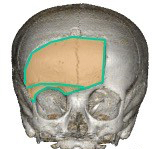

la voie sous-frontale nécessite de principe la dépose du rebord orbitaire, qui permet un accès vers le haut sans rétracter le lobe frontal, mais nécessite souvent une cranialisation du sinus frontal.

assister au cours sur l’abord sous-frontal des tumeurs supra-sellaires avec dépose du rebord orbitaire